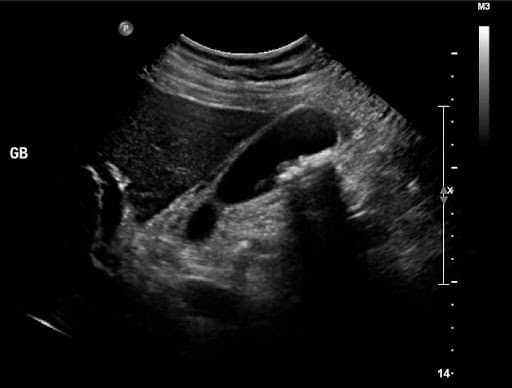

– Siêu âm vùng ổ bụng: Hình ảnh hiển thị được tạo ra bởi các sóng âm. Siêu âm ổ bụng sẽ cho kết quả nhanh nhất và cũng được sử dụng nhiều nhất trong chẩn đoán viêm túi mật cấp.

Khi có kết quả xét nghiệm, bác sĩ sẽ xác định được độ dày mỏng của thành túi mật, xác định túi mật có sỏi hay không và phần viêm sưng, biến chứng nếu có. Từ đó sẽ có chỉ định điều trị ngay cho phù hợp.

Viêm túi mật cấp cần được chẩn đoán chính xác qua siêu âm, chụp X – quang, CT…